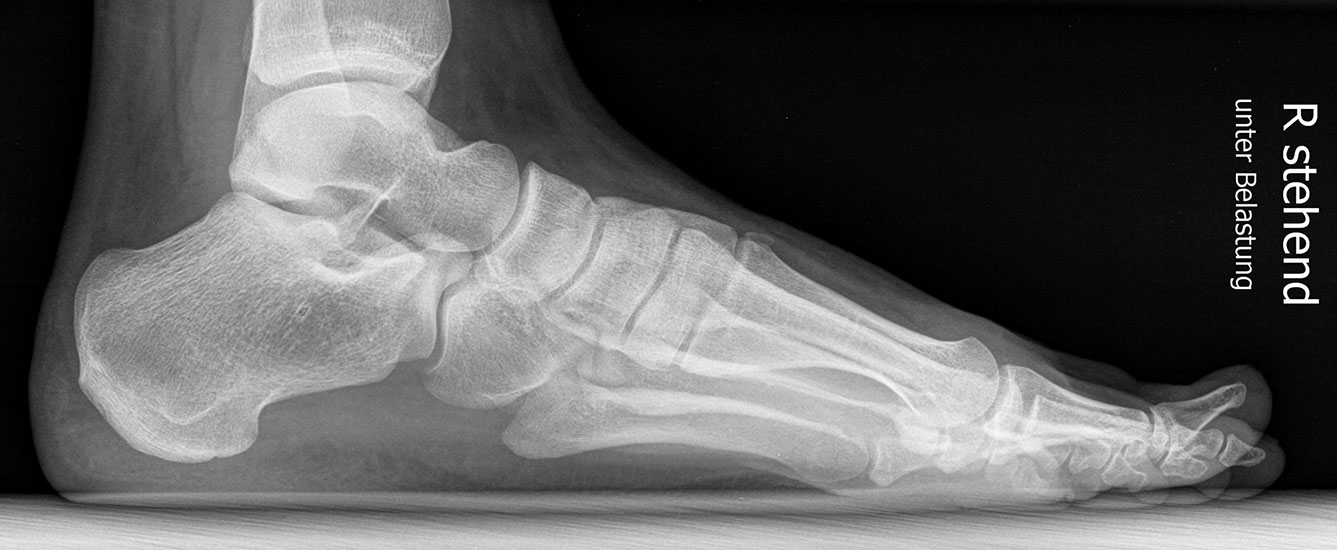

Standard ist die belastete Röntgenaufnahme des Fußes dorso-plantar und seitlich. Günstig ist eine Röhrenkippung von 10°-20°, um die Gelenke der Lisfranc-Linie einsehen zu können.

Ergänzend kann eine Schrägaufnahme hilfreich sein. Bei Metatarsalgien oder Pathologien der Sesambeine liefert die Sprinteraufnahme zusätzliche Informationen. Bei einer Pes planovalgus Fehlstellung wird ergänzend ein Saltzman view durchgeführt.